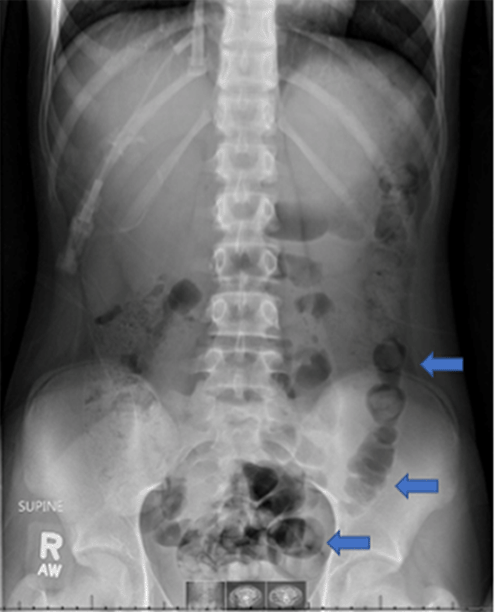

A 13-year-old female with newly diagnosed high-risk precursor B cell acute lymphocytic leukemia (ALL) presented to the emergency department (ED) with worsening abdominal pain on day 14 of her induction chemotherapy (vincristine and daunorubicin). The pain was located in the mid-abdomen, which was described as generalized, worse with movement or palpation. She denied nausea, vomiting, and diarrhea but endorsed recent constipation. The patient was seen the day prior in the ED with abdominal discomfort and was discharged with the diagnosis of constipation (Figure 1).

Figure 1. Abdominal X Ray Suggestive of Colon Containing Stool (blue arrows). Published with Permission

Abdominal X Ray Suggestive of Colon Containing Stool (blue arrows).